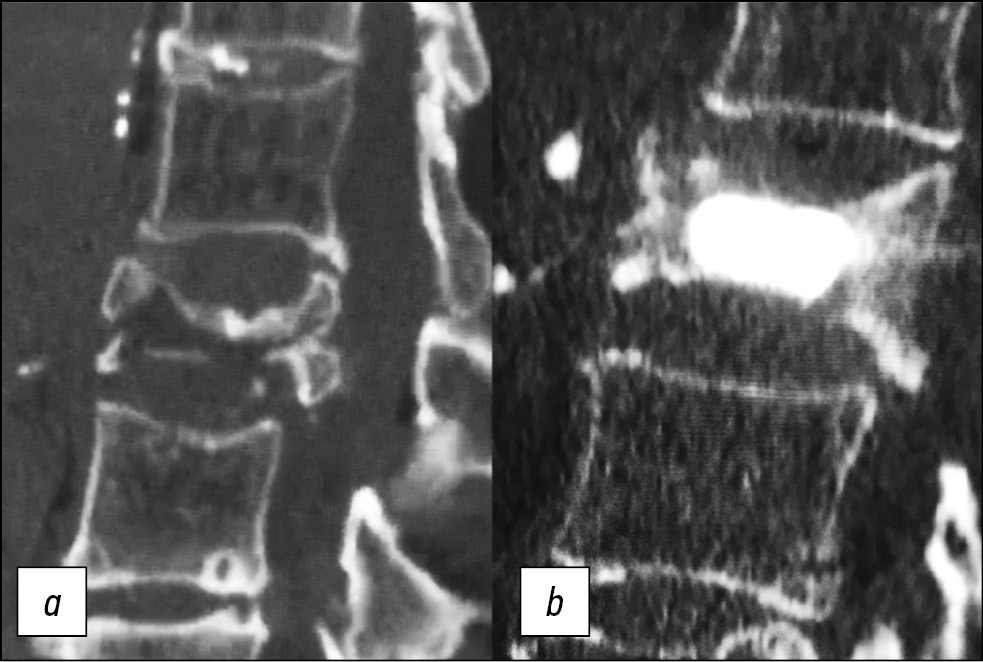

We observed a significant decrease in ODI values from a preoperative mean of 73.2±7.9 to the mean values of 14.1±3.3, 13.8±3.6, and 14.0±2.9 at 1-, 6-, and 12-months follow-up, respectively (p < 0.05) (Fig. 3).

Fig. 3. (a): CT scan: Sagittal reconstruction of a complex vertebral fracture. (b): Post-operative CT control. Vessel-X is perfectly placed without BFM leakage.